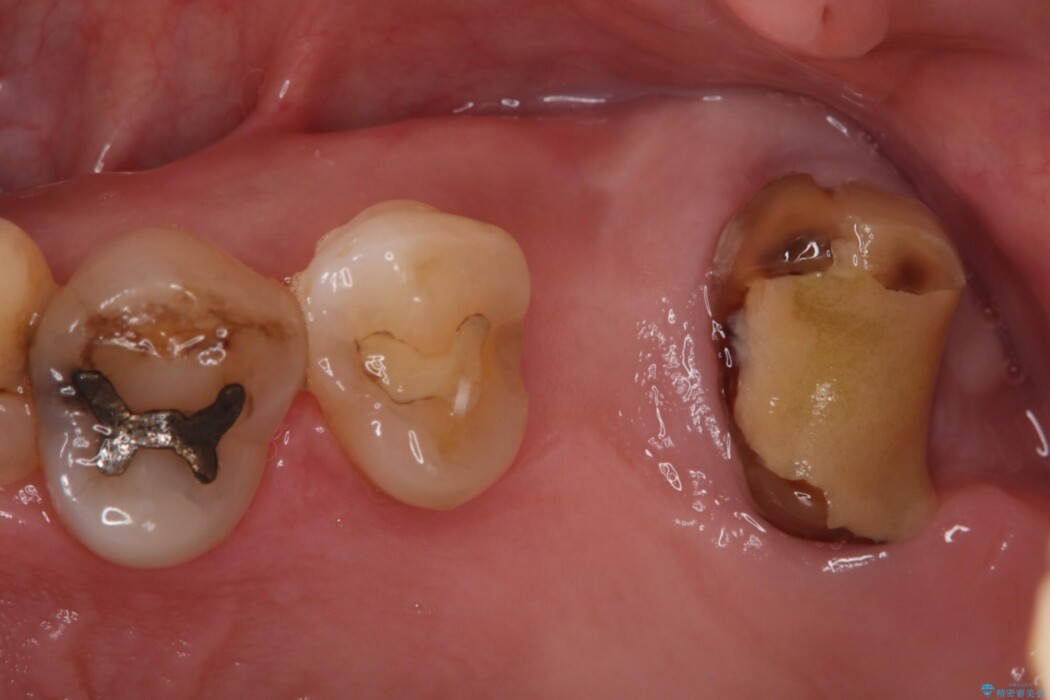

精密検査の結果、治療を中断していた左上7番は重度の虫歯や歯周組織の崩壊により保存が難しい状態でした。

6番も歯を失ってから時間が経っていたため、奥歯でしっかりと噛むことができない状態でした。

7番については抜歯と同時にインプラントを埋入する「抜歯即時埋入法」を選択。通院回数と治療期間を大幅にカットすることで患者様の負担を減らします。